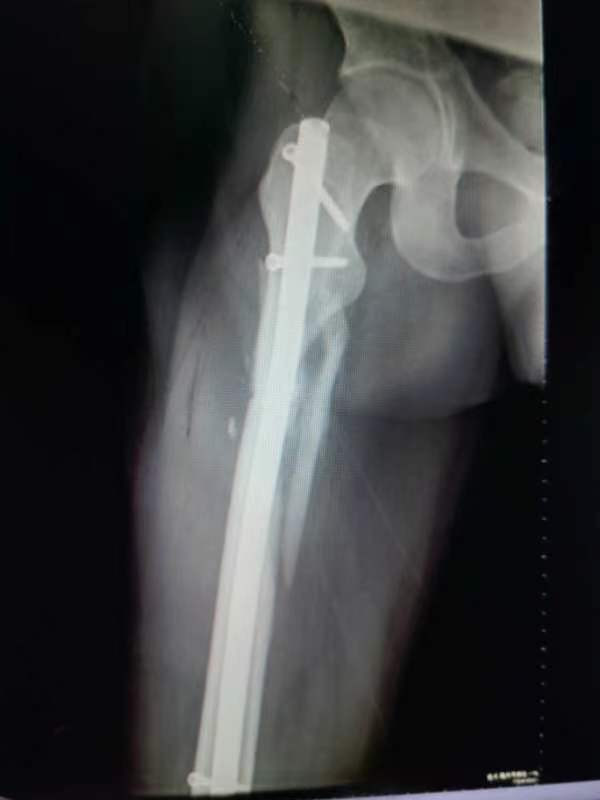

中股网 外伤导致的股骨上段骨折闭合复位股骨重建钉固定,期待早期愈合